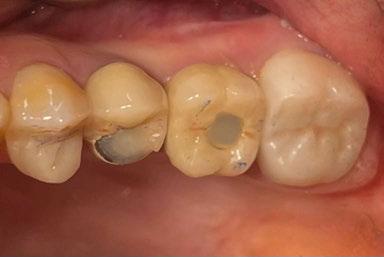

A partir del estudio radiológico y de las imágenes fotográficas podemos observar edentulismo de 17, 15, 14, 12,

Figura 1a. Foto intraoral frontal inicial.

Figura 1b. Foto intraoral lateral izquierda inicial.

Figura 1c. Foto intraoral lateral derecha inicial.

Cuadro 1. Protocolo fase planificación, quirúrgica y protésica.

25, 26, 28, 37, 38, 47 y 48. Presentaba corona desajustada en 13 con extensión en 12, implantes en 35-36, 45-46, con coronas ferulizadas en 35-36, 45-46, y dientes anteriores superiores con enfermedad periodontal Grado IV.